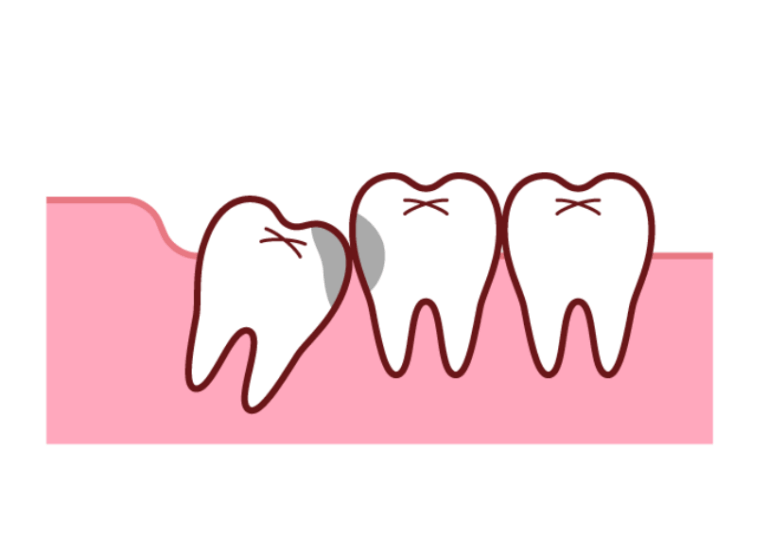

スペースが足りないことで親知らずは私たちの予想もしないような生え方をすることがあります。

横や斜めに生えてくる

スペース不足のためまっすぐ上に出てくることができず、横向きや斜めに傾いて生えてきてしまうケースです。

隣にある大切な奥歯(第二大臼歯)をぐいぐいと押し続け、歯並び全体を乱してしまったり強い痛みの原因となったりします。